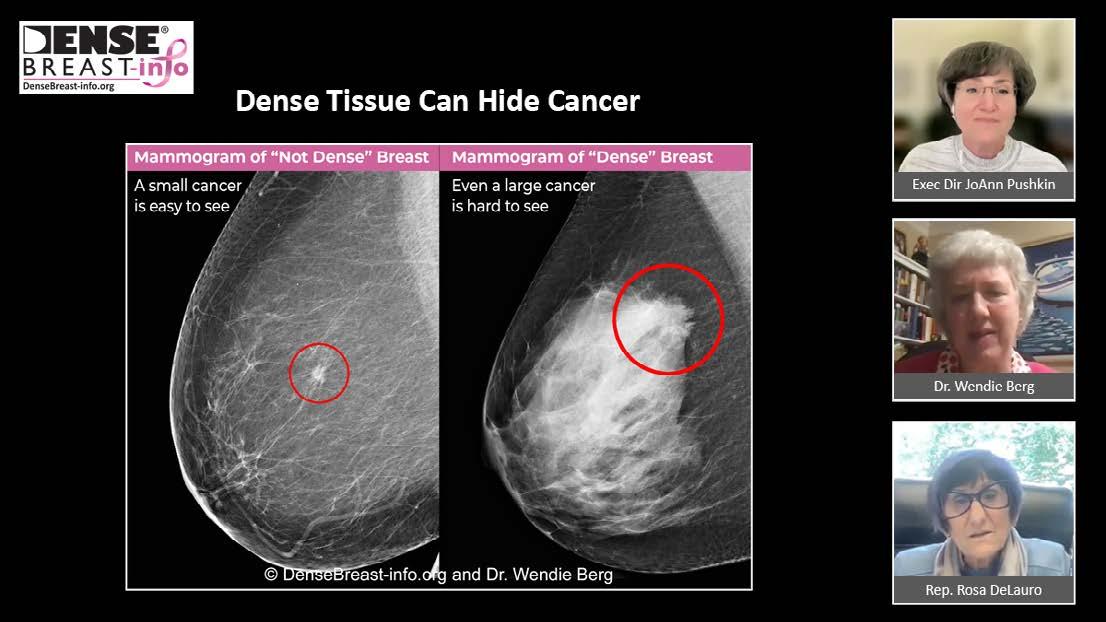

DenseBreast-info.org (DBI) was launched in 2015 to educate patients and clinicians about the screening and risk implications of dense breast tissue and to inform discussions about supplemental screening. The site’s Medical Advisory Board, led by Dr. Wendie Berg, is composed of internationally recognized, published experts in breast imaging and obstetrics/gynecology. The website supports advocacy, education, legislation, and policy conversations. It is now the world’s leading website on the topic and is on track to host over 1 million website visits in 2024 alone.

Screenshot from a national press briefing on the FDA dense breast reporting rule with DBI’s JoAnn Pushkin, Dr. Wendie Berg, and Rep. Rosa DeLauro.